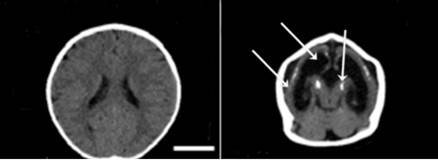

With this in mind, we travelled to different Brazilian States where CZS cases had been reported to search for newborn twins. We intended to examine them personally. Among 91 CZS newborns, we identified nine pairs of twins from different Brazilian regions with at least one affected baby: seven DZ and two MZ. The two MZ pairs of twins were concordant (both affected) but six among the seven DZ twins pairs were discordant. This distribution was compatible with our hypothesis of a genetic predisposition increasing the risk for CZS.

Eventually, we were able to obtain samples and derive NPCs from three pairs of discordant twins. No decrease in cell proliferation prior to in vitro ZIKV infection was observed in NPCs from affected twins as compared to the normal ones suggesting that, if the affected twin had not been infected by ZIKV, most likely his/her neurodevelopment would not be impaired. Next, we infected with ZIKV the NPCs from these six babies in the same laboratory conditions. What was observed then?

ZIKV replicated and reduced cellular replication in affected NPCs significantly more than in the normal babies supporting our hypothesis. We were very excited. Results “in vitro” seemed to replicate what happened “in vivo”. Could genetic/epigenetic factors explain such differences? To address this question, we analyzed global gene expression profile in the three non-affected as compared with the three affected twins and confirmed there were significant differences in key regulators of neurodevelopment and regionalization. Interestingly, such differences in the gene expression programs were observed in NPCs cells prior to infection.